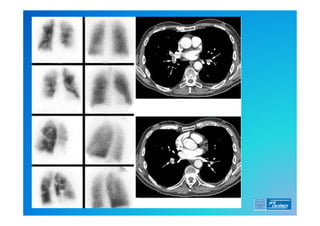

8) Cintilografia Pulmonar (Ventilação/Perfusão)

Diagnóstico . 0) EXAME FÍSICO 1)ECG (alterações frequentes ?) 2) RX de Tórax (o que esperar ?) 3) Laboratório (o que é importante ?) 4) D Dimero 5) Doppler Venoso MMII 6) Ecocardiograma (TT e TE) 7) Angio TC 8) Cintilografia Pulmonar (Ventilação/Perfusão) 9) Angio RM 10) Arteriografia